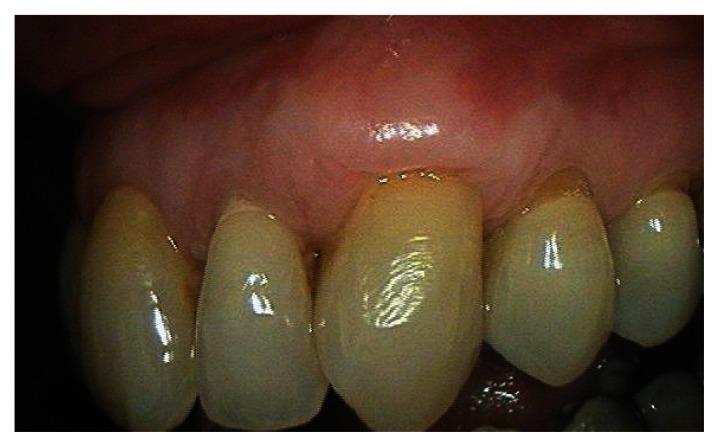

This case report describes the treatment of a maxillary canine that had 4 mm of marginal gingival recession. The exposed root had been previously restored with a composite class 5 restoration. The restoration was removed and the root planed and demineralized. The root was then covered by a subepithelial connective tissue graft harvested from the palate. The flap was coronally positioned to completely cover the graft and exposed root. The healing was photographed post-operatively at one month, six months, and seven years. Root coverage increased to 100% after seven years. The zone of attached gingiva also increased.